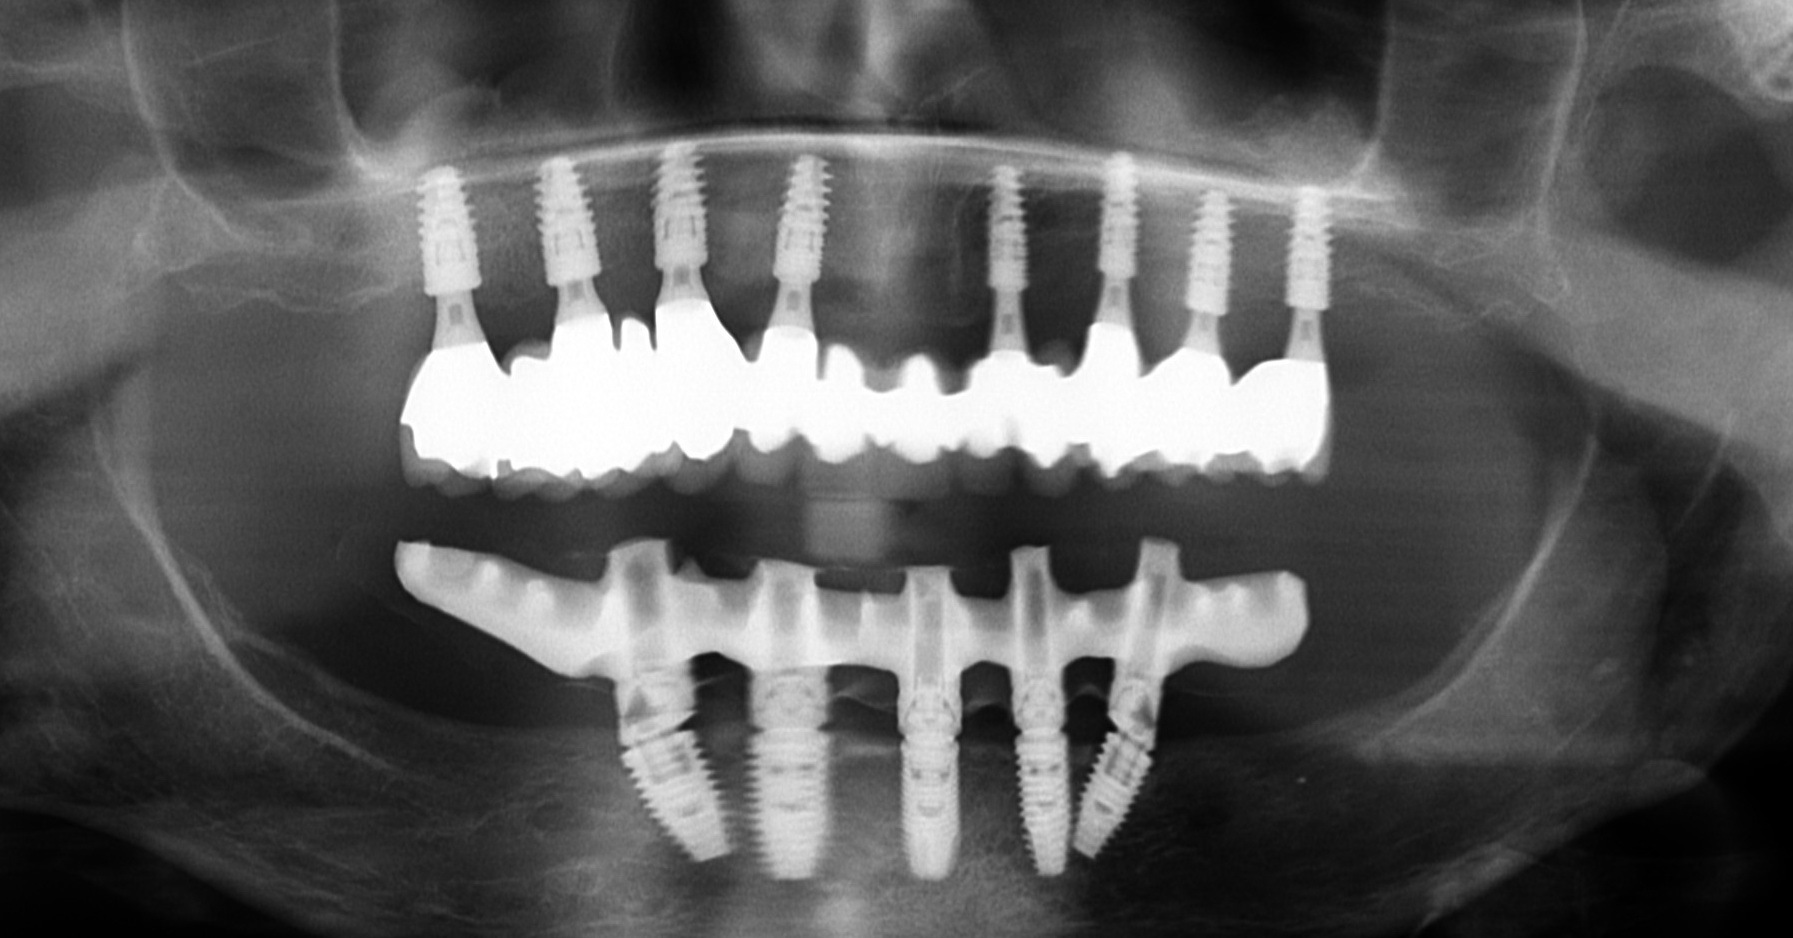

- Cas 1: Contrôle radiologieque des armatures usinées

L’usinage des armatures en titane, chrome-cobalt ou zircone des prothèse sur implants génère une précision d’adaptation inégalée en 2014 objectivable à la radiologie. L’usinage permet également une étanchéité des restaurations, une solidité accrue et un gain de temps considérable puisque les essayages sont rapides et de nouvelles empreintes rares. Ces armatures sont usinées en Suède ou aux USA pour le système Procera de Nobel Biocare.

Dans les cas de bridges complets (ici mandibulaire), l’usinage des armatures permet une adaptation passive des pièces et un vissage sans tension des vis. La pérennité de la réhabilitation en est augmentée.

La zircone est un éléments métallique de couleur BLANCHE. Huit microvis stabilisent le bridge sur les huit implants maxillaires.

L’aspect radiologique des deux types de bridges est différent. Le bridge complet en « zircone-céramique » est réservé pour le maxillaire car ce sont les dents maxillaires qui sont les plus visibles lors du sourire et car il ne faut faire se rencontrer deux bridges complets sur implants en « zircone-céramique » en raison du risque de fracture de la céramique dans cette combinaison. L’hygiène interimplantaire au moyen des brossettes est l’élément clé du succès et du confort à long terme de ces traitements.